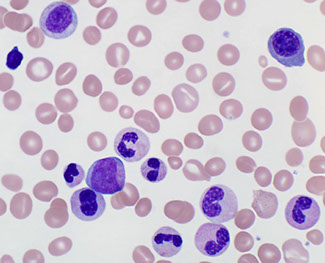

Juvenile MyeloMonocytic Leukemia (JMML)

Childhood disorder (male predominance) with granulocytic and monocytic proliferation with low blast counts and characteristic RAS/MAPK mutations, usually minimal dysplasia

- assoc c NF1 (10-20% of cases; thus not a criterion)

- kids c Noonan syndrome get a JMML-like dz that resolves spontaneously

- Blasts + Promonos <20% in PB and BM

Present c S-megaly, enlarged tonsils, B symtoms, inc HgF, can have skin and spleen infiltrates

Diagnostic criteria:

I. Clinical + hematologic features (need all 4)

1.) Monocytosis in PB

2.) (Blasts + promyelocytes) <20% in PB and BM; (will never see Auer rods)

3) Splenomegaly

4.) No Ph chr or BCR-ABL1 fusion gene

II. Genetic findings (1 sufficient)

- Somatic PTPN11 or KRAS or NRAS

- Clinical diagnosis of NF or NF mutation

- Germline CBL mutation and LOH of CBL

III For pts w/o genetic features, besides the clinical and hematologic features under I, must have:

- monosomy 7 or any other chromosomal abnormality, or at least 2 of the following:

- Inc HbF; Immature granulocytes in PB; GM-CSF hypersensitivity of myeloid progenitor cells in vitro; hyperphosphorylation of STAT5

PB is most important in dx'ing; see anemia, inc leukos and Tbcpenia

- napthyl acetate/butyrate acetase c NAE good for viz monocytes

Can mimic infx (Ebstein-Barr, CMV, herpes)

~65% have normal karyotype, ~25% monosomy 7

- BCR/ABL1 negative

- RAS and MAPK pathway mutations are characteristic

- PTPN11 gene mutations, SHP-2 phosphatase

- RAS gene mutations

- NF1 gene inactivation

Increased cellular sensitivity to GM-CSF

Hematopoietic stem cell transplantation

Monosomy 7 in 25%; 65% have normal karyotype

DDx: Leukemoid reaction, CML (can occur in kiddos, but very rare), kids c Noonan syndrome have PTPN11 mutation encoding SHP2 or in KRAS

Px: Rapidly fatal if left untreated

- need stem cell transplant or die in 1 year

-- rarely transforms to AML

JMML - myeloid predominance with a left-shift